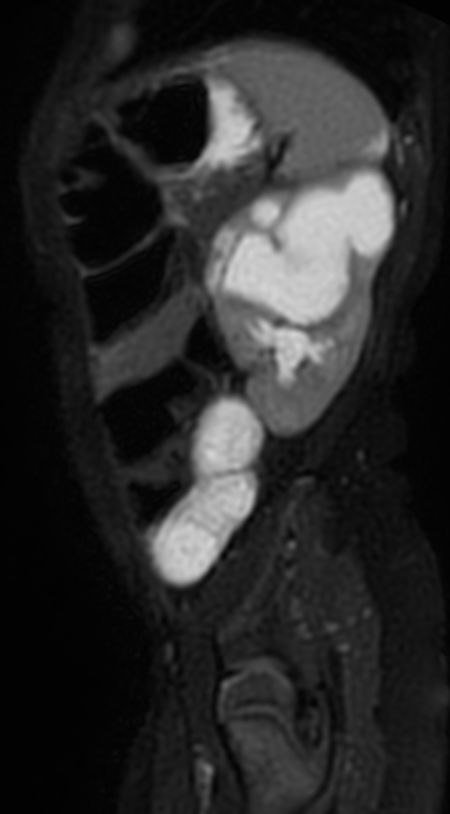

3D VIEW T2w SPIR - Sagittal reformat